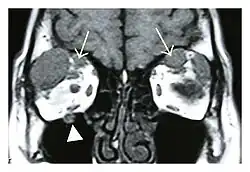

The extent of inflammation that can occur in IgG4-ROD is well demonstrated on magnetic resonance imaging (MRI).

Swelling of the left superior and lateral rectus muscles, a mass lesion around the left optic disc (arrow), and enlargements of the left supraorbital nerve and the right infraorbital nerve (arrow heads) in a 60-year-old man with a serum IgG4 of 463 mg/dL.[1] (T1-weighted MRI)

Bilateral supraorbital nerve enlargements (arrows) and right infraorbital nerve (arrow head) enlargement in a 47-year-old woman with a serum IgG4 of 1000 mg/dL.[1] (T1-weighted MRI)